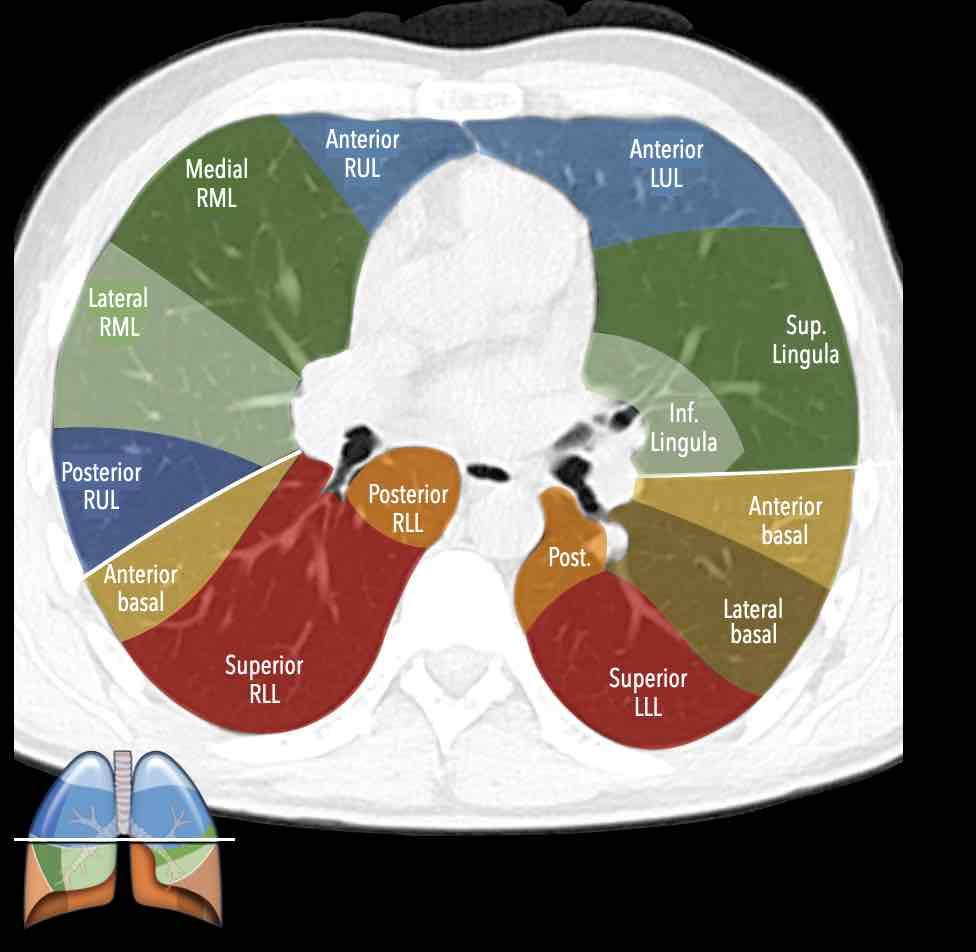

Thùy trên phổi phải (màu xanh lam)

Phân thùy đỉnh (RB1) – Phân thùy sau (RB2) – Phân thùy trước (RB3)

Thùy giữa (màu xanh lá)

Phân thùy bên (RB4) – Phân thùy trong (RB5)

Thùy dưới phổi phải (màu cam)

Phân thùy trên (RB6) – Phân thùy đáy trong (RB7) – Phân thùy đáy trước (RB8) – Phân thùy đáy bên (RB9) – Phân thùy đáy sau (RB10).

Thùy trên phổi trái (màu xanh lam)

Phân thùy đỉnh-sau (LB1/2) – Phân thùy trước (LB3)

Lưỡi phổi (màu xanh lá)

Phân thùy trên (LB4) – Phân thùy dưới (LB5)

Thùy dưới phổi trái (màu cam)

Phân thùy trên (LB6) – Phân thùy đáy trước (LB8) – Phân thùy đáy bên (LB9) – Phân thùy đáy sau (LB10).

Giải phẫu phân thùy của hai phổi có tính đối xứng nhất định, vì phổi trái chỉ khác phổi phải một chút.

Phổi phải có ba thùy (gồm thùy trên, thùy giữa và thùy dưới) với mười phân thùy,

trong khi phổi trái có hai thùy (gồm thùy trên và thùy dưới) với số phân thùy ít hơn.